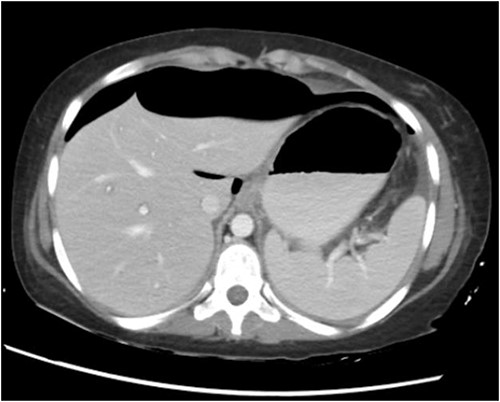

CT abdomen with oral and intravenous contrast was done, which revealed gross pneumoperitoneum, significantly dilated stomach with dilated multiple small bowels loops up to the distal ileum with no evidence of contrast extravasation. Moderate ascites with mesenteric congestion were seen (Fig. 2).